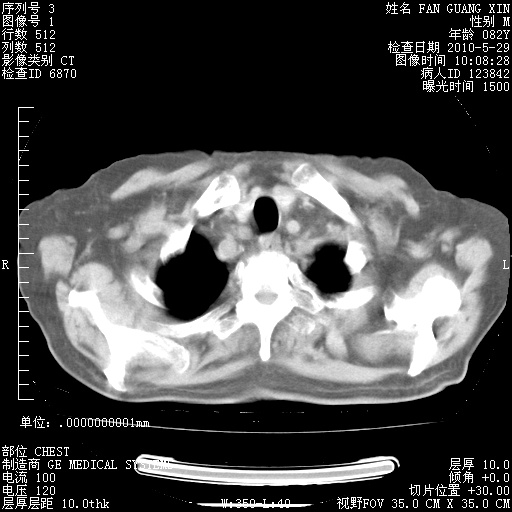

还需要哪些辅助检查?我们医院排除真菌感染没有任何检验方法,胸片好像能够排除肺部真菌感染。